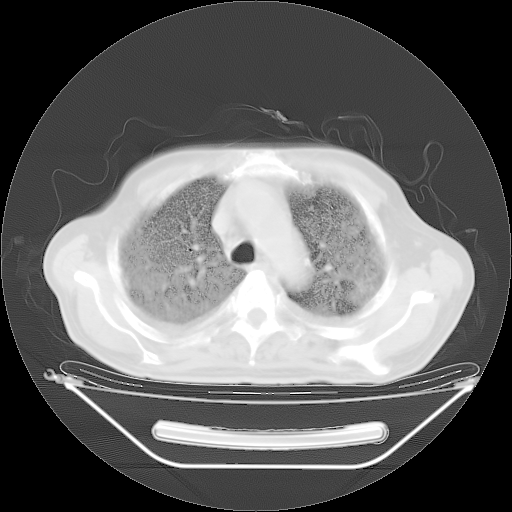

今天复查肺部CT,发现双肺广泛磨玻璃样改变。所以我把3月19日和5月9日相隔50天的肺部CT上传。请大家会诊。

2009年3月19日肺部CT片。

2009年3月19日肺部CT